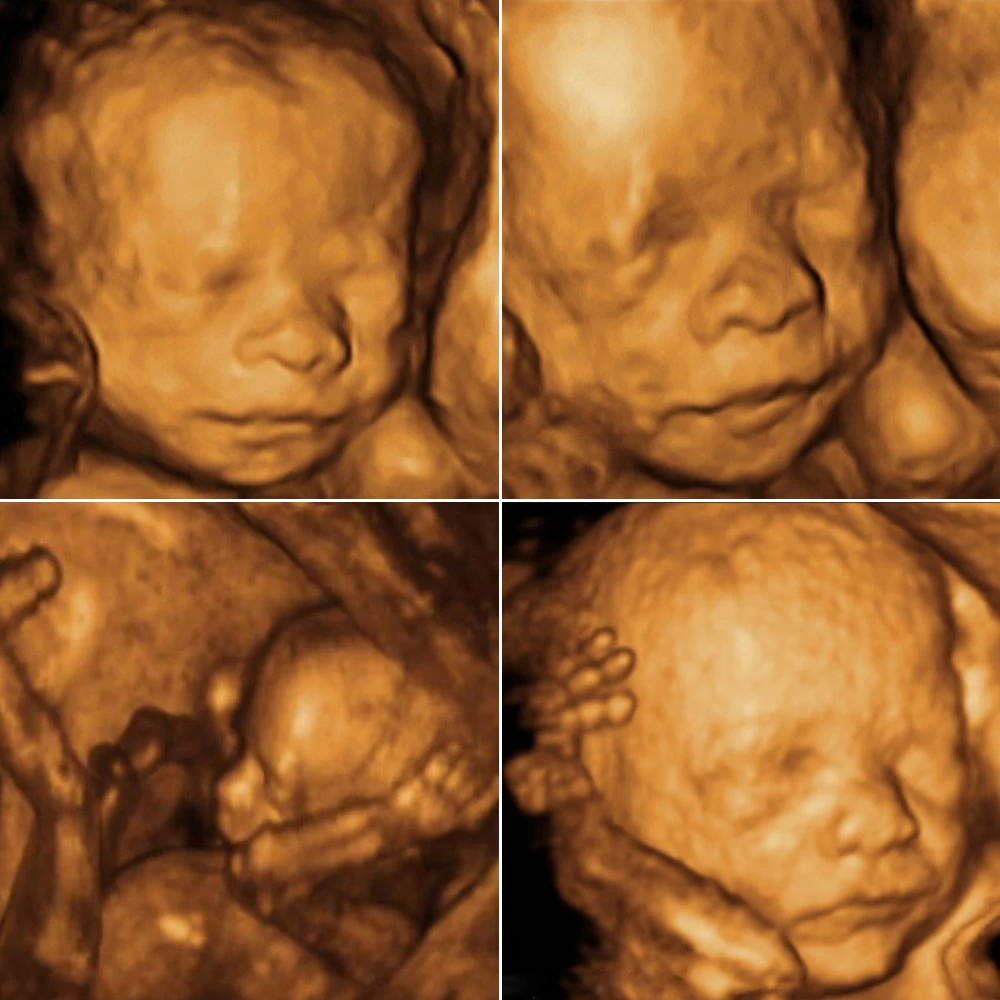

Неделя № 8

Тело эмбриона начинает выпрямляться, длина от темени до копчика составляет 15 мм в начале недели и 20-21 мм на 56 день, лицо ребенка становится привычным для человека: хорошо выражены глаза, прикрытые веками, нос, ушные раковины, заканчивается формирование губ.Отмечается интенсивный рост головы, верхних и нижних конечностей, начинается окостенение длинных костей рук и ног и черепа. Хорошо заметны пальцы. Восьмой неделей заканчивается эмбриональный период развития. Зародыш с этого времени называется плодом.